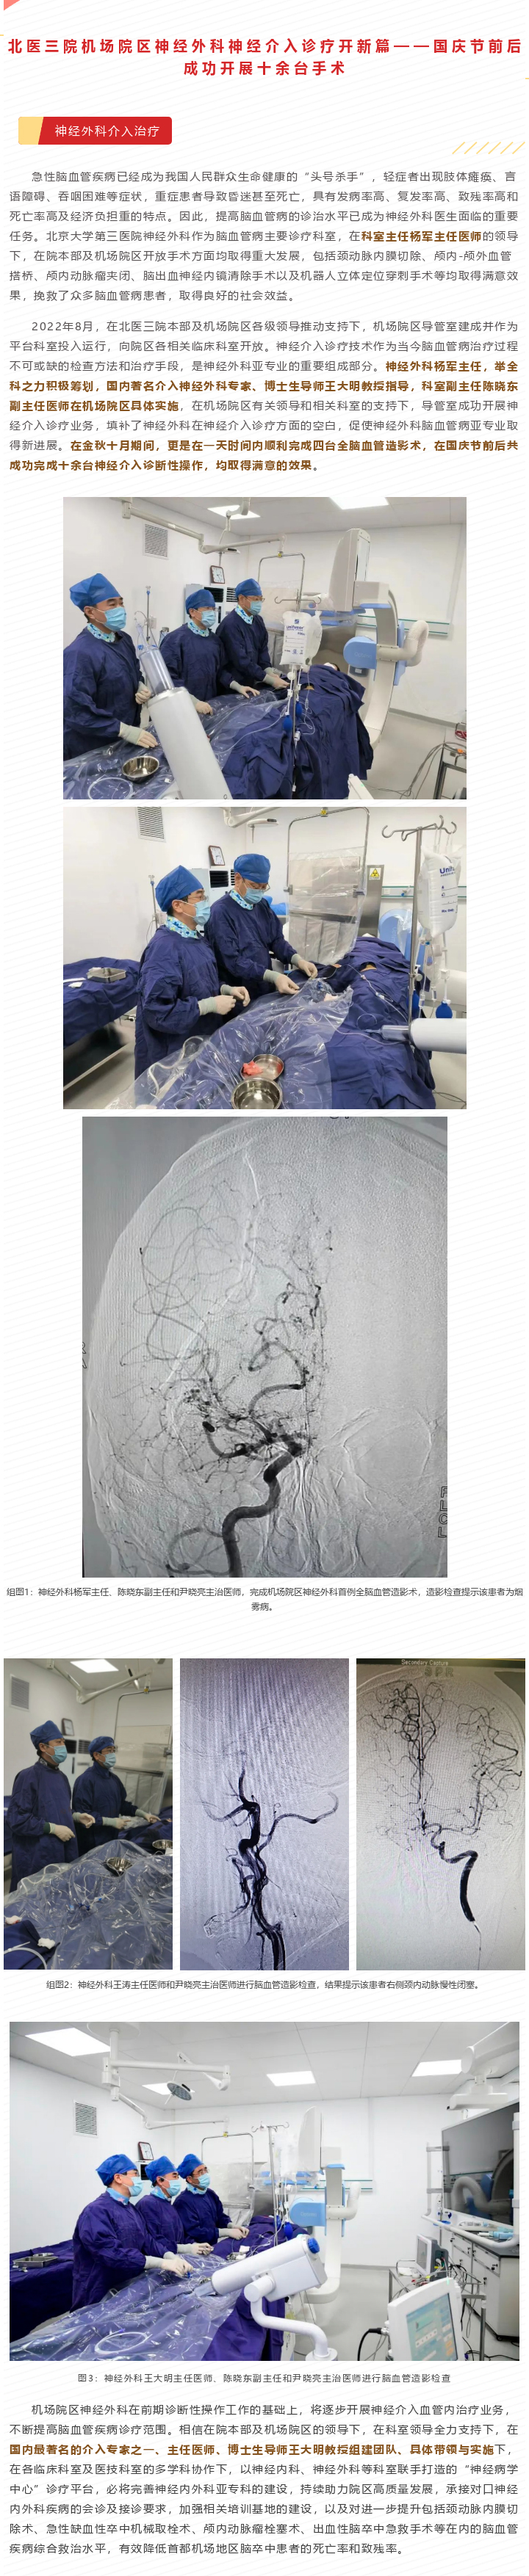

北医三院机场院区神经外科神经介入诊疗开新篇——国庆节前后成功开展十余台手术